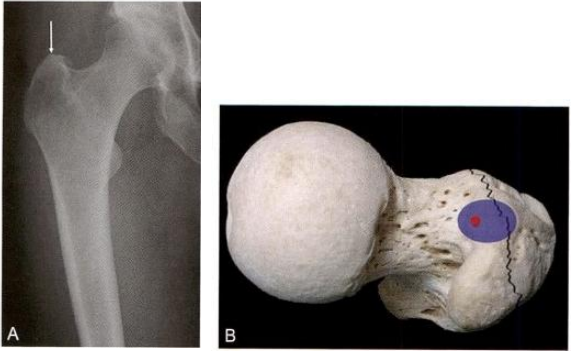

术毕透视,示骨折复位质量优(4分),内固定稳定性优(8分)。术 后三维CT 证实前内下角获得骨皮质对骨皮质的可靠支撑。术后1周,患 者在搀扶下可下地负重站立,练习行走。随访1.5年,骨折完全愈合(图 9-21)。

图9-21 小转子二分型难复位骨折。A.术前X 线片示股骨转子间二部分骨折,小转 子被骨折线平均分为上下两块,分别与头颈骨块和股骨干相连;B. 外上角骨性交锁 (箭头);C.三维CT重建图像,显示典型的移位特征:头颈骨块屈曲外旋,股骨干上 移短缩,头颈骨块下方骨皮质尖齿骑跨于股骨干前方